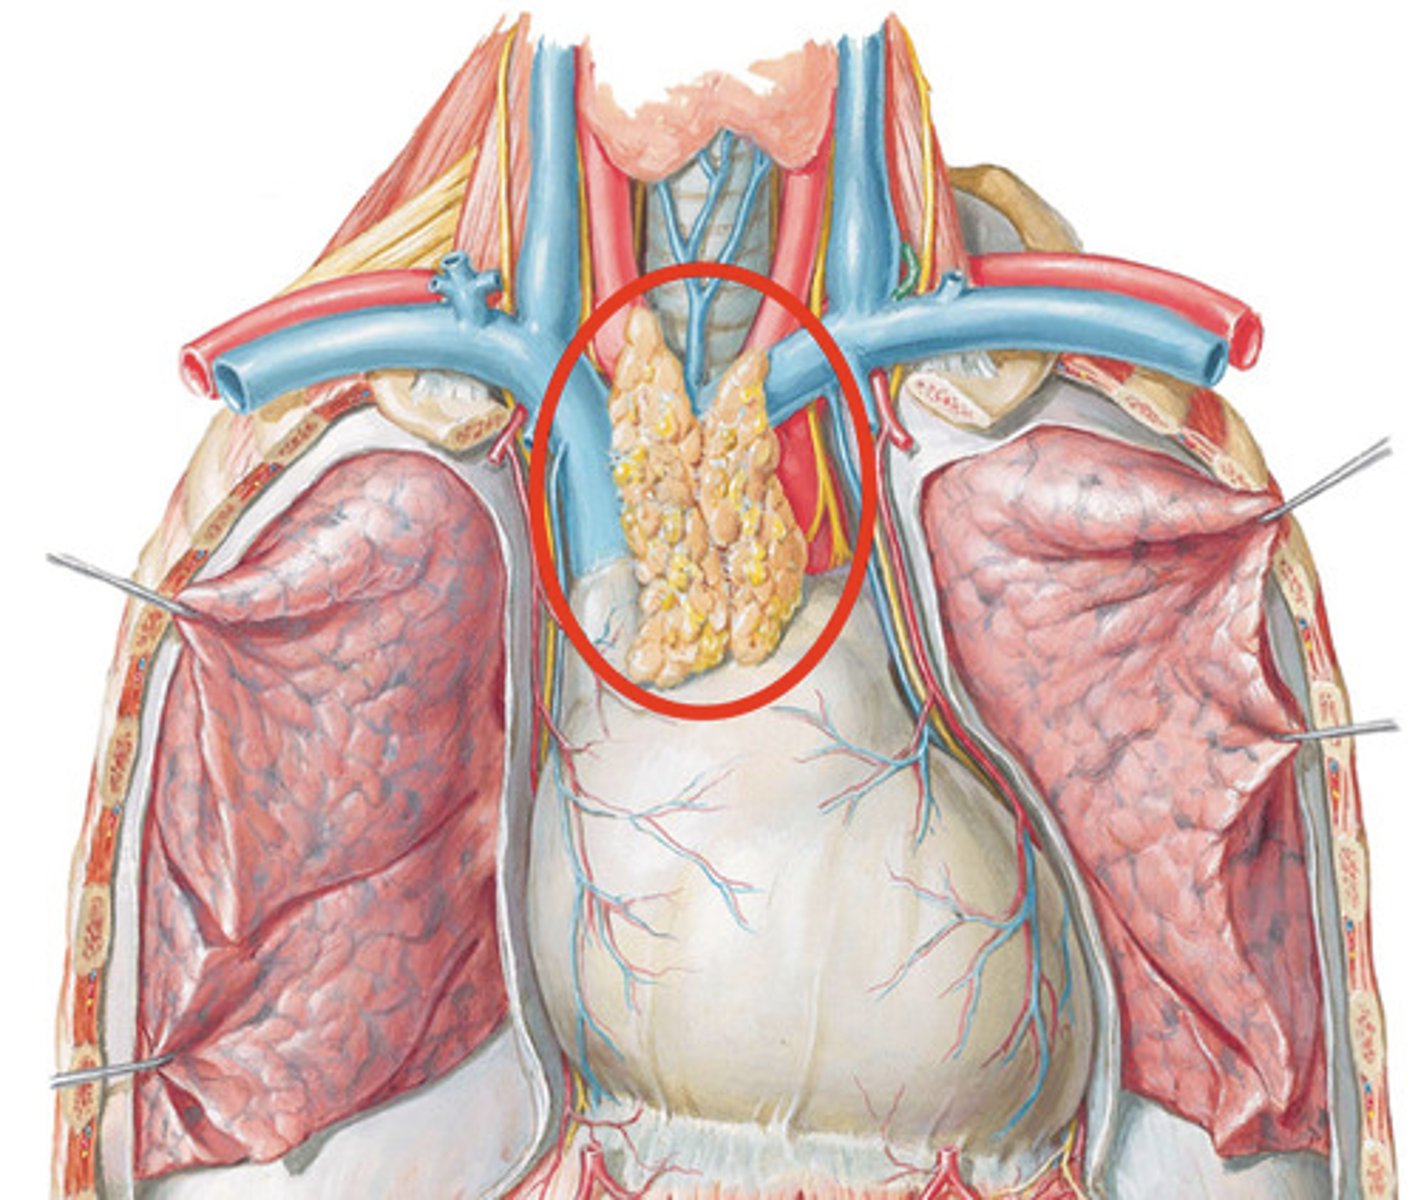

What does the thymus do?

Site of T cell differentiation and maturation

T cells

A type of lymphocyte that is created in the thymus; produce substances that attack infected cells in the body